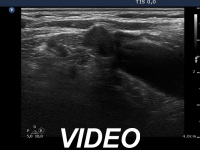

Ultrasonography: the right thyroid was echonormal while the left lobe contained moderately hypoechogenic areas with a 50% echogenicity index. There was a hypoechogenic mass lower and lateral to the right thyroid. The lesion did not present a regular hilum.